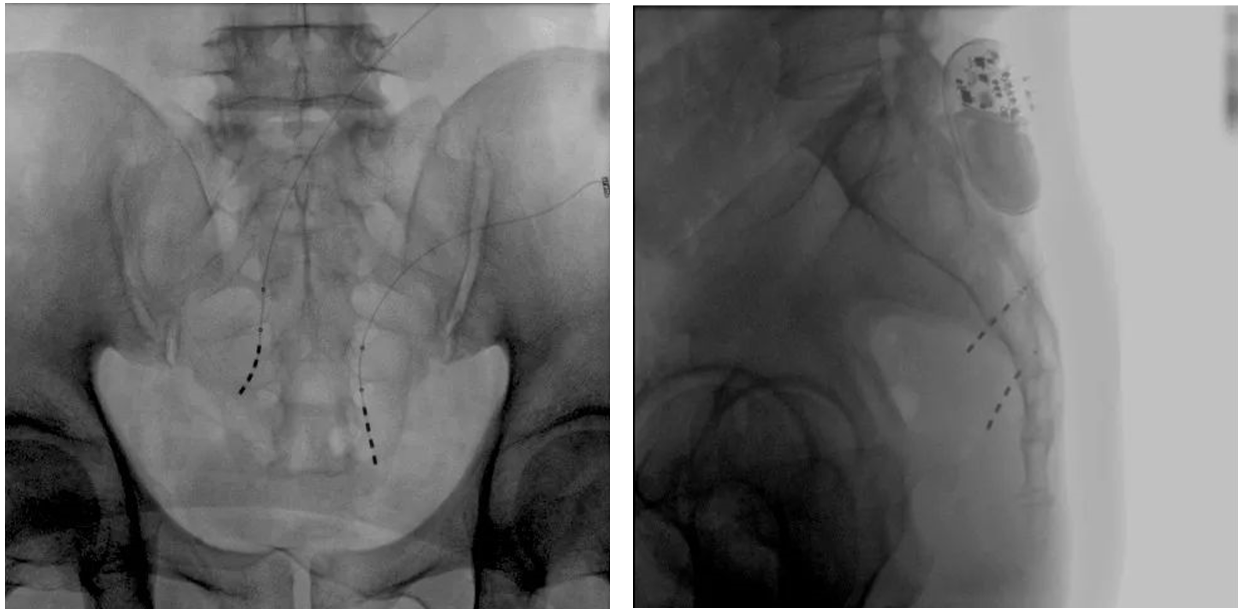

患者術前影像

大平板一體式移動C形臂術中影像